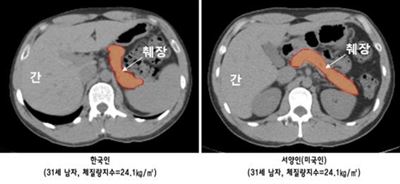

ÀÓ¼ö ºÐ´ç¼­¿ï´ëº´¿ø ³»ºÐºñ³»°ú ±³¼öÆÀÀº ÄÄÇ»ÅÍ´ÜÃþÃÔ¿µ(CT)À» ÅëÇØ ü°ÝÀÌ À¯»çÇÑ 30´ë Çѱ¹Àΰú ¼­¾çÀÎÀ» 43¸í¾¿ À̵éÀÇ ÃéÀå ¿ëÀû µîÀ» ºñ±³ ºÐ¼®ÇØ ÀÌ·± »ç½ÇÀ» È®ÀÎÇß´Ù°í ¹àÇû´Ù.

¿¬±¸ÆÀ¿¡ µû¸£¸é Çѱ¹ÀÎÀº ¼­¾çÀκ¸´Ù ÃéÀåÀÇ Å©±â°¡ 12.3% Á¤µµ ÀÛÀº ¹Ý¸é ÃéÀå¿¡ Ä§ÂøµÈ Áö¹æÀÇ ¾çÀº 22.8% ¸¹¾Ò´Ù.

ÃéÀåÀÇ Àν¶¸° ºÐºñ ´É·ÂÀº Çѱ¹ÀÎÀÌ ¼­¾çÀκ¸´Ù 36.5% ¶³¾îÁö´Â °ÍÀ¸·Î ³ªÅ¸³µ´Ù.

Çѱ¹Àΰú ¹Ì±¹ÀÎÀÇ ÃéÀå Å©±â ºñ±³. °°Àº ³ªÀÌ, µ¿ÀÏ Ã¼Çü¿¡¼­ ¼­¾çÀκ¸´Ù

Çѱ¹ÀÎÀÌ ÃéÀå Å©±â°¡ ÀÛ°í ÃéÀå³» Áö¹æ Ä§ÂøÀº ¸¹´Ù. ºÐ´ç¼­¿ï´ëº´¿ø Á¦°ø